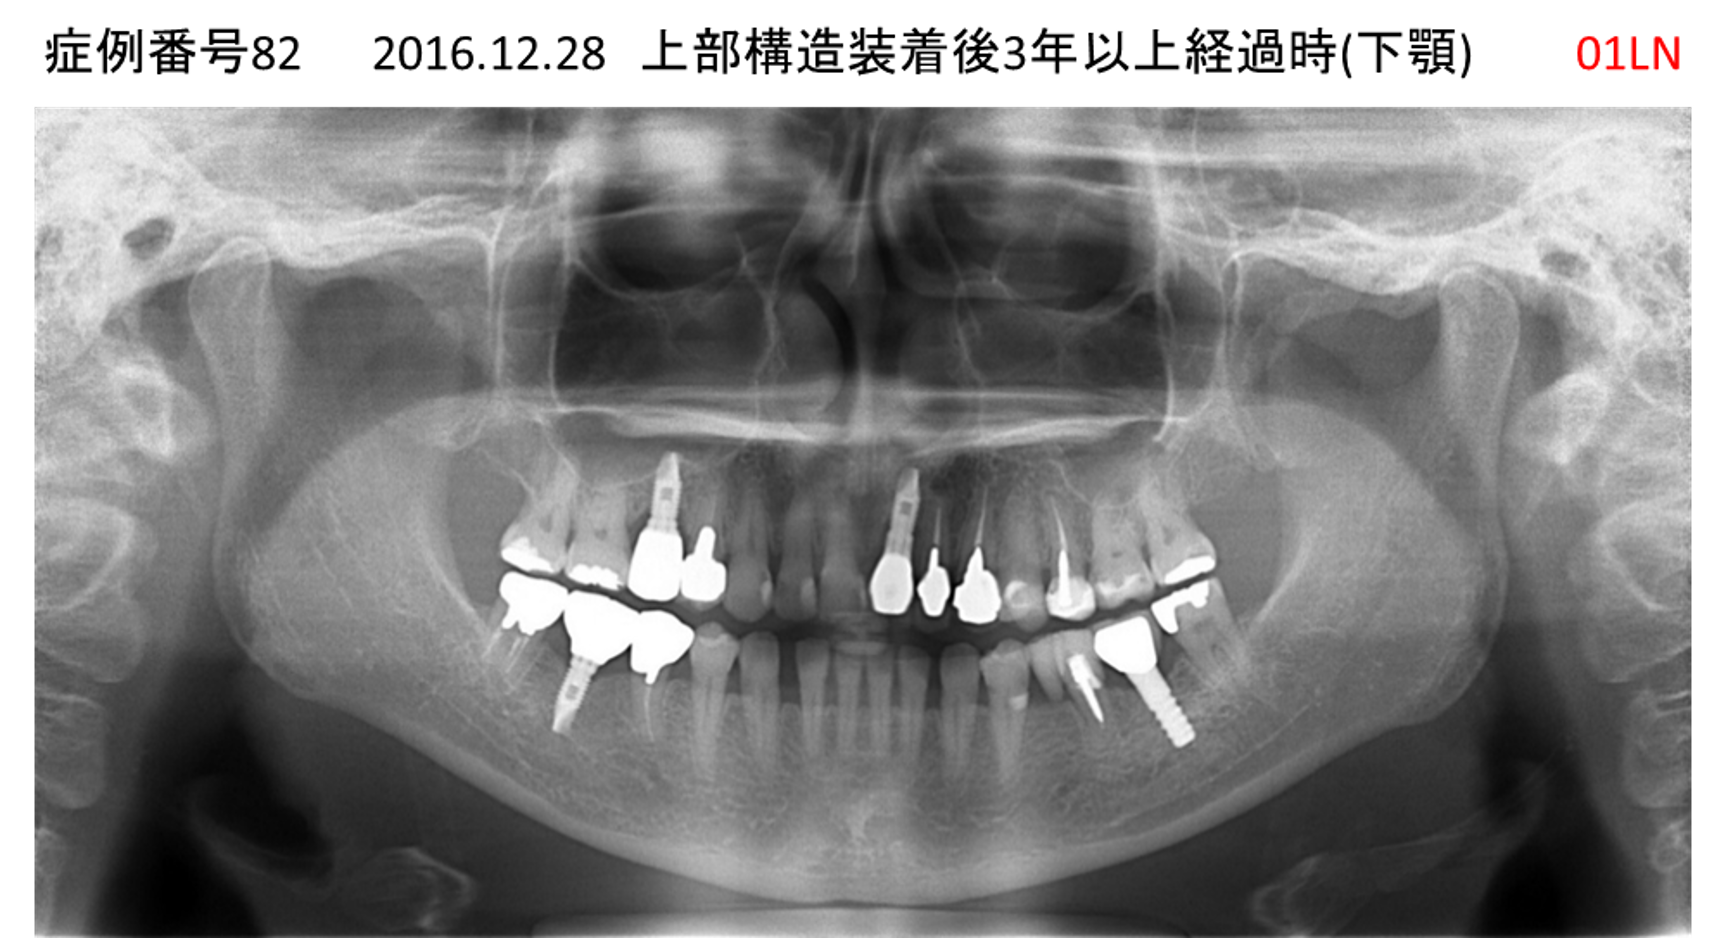

左下の奥歯が痛い患者様のインプラント症例

| 治療名称 |

インプラント |

| 治療費用 |

215万円+税 |

| 治療期間 |

5か月 |

| 患者さんの症状(主訴) |

左下の奥歯が痛い。 |

| 治療内容 |

| 治療結果 |

痛み無く、噛める。 |

| 治療の注意点(リスク/副作用) |

インプラントが壊れたら再治療が必要 |